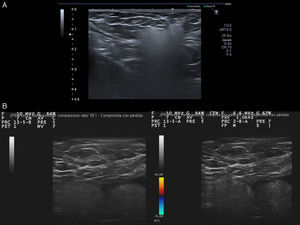

Caso clínico 1Mujer de 49 años con historia de melanoma dorsal izquierdo en estadio IA de la AJCC en el año 2006. En enero de 2014 la paciente refería palparse un bulto en la axila izquierda. A la exploración se trataba de una lesión nodular subcutánea de aproximadamente 2cm, de tacto firme, no adherida a planos subyacentes. Con la sospecha de adenopatía metastásica se remitió al servicio de radiodiagnóstico para realizar una ecografía. En la ecografía (Toshiba Aplio 500, sonda lineal multifrecuencia 7-11MHz) se visualizó una imagen hiperecogénica difusa con mala transmisión sonora, de 2cm de diámetro mayor, localizada en el tejido subcutáneo (fig. 1A). Esta imagen ecográfica se ha descrito como en «tormenta de nieve», y es altamente sugestiva de siliconoma por rotura de prótesis mamaria. Tal es así que en el mismo acto se realizó una ecografía mamaria, apreciándose gel extravasado al espacio comprendido entre el pliegue de la cubierta externa de la prótesis y la cápsula externa fibrótica, hallazgo que confirmó la rotura capsular de la prótesis mamaria izquierda (fig. 2). En la anamnesis la paciente confirmó haberse implantado unas prótesis Poly Implant Protheses (PIP) en el año 2008.

A. Imagen hiperecogénica localizada en tejido celular subcutáneo, de morfología arriñonada, ecoestructura homogénea de límite superior y laterales nítidos y pérdida de borde profundo por artefacto en tormenta de nieve. B. Dos imágenes hiperecogénicas adyacentes pseudoencapsuladas en «tormenta de nieve» en tejido subcutáneo. Ausencia de vascularización con doppler color.